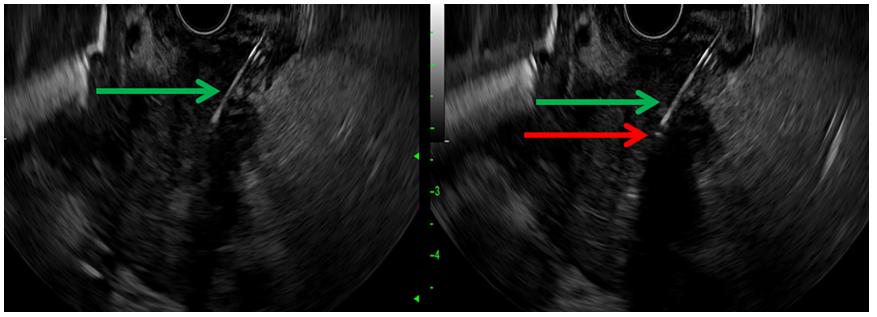

具体内镜操作过程如下。于-28天至0天进行高分辨率、增强对比的胰腺CT扫描。第0天,在光动力治疗前60~90 min以0.4 mg/kg的剂量方案静脉注射维替泊芬。如果有过敏反应,患者需要于术后预防性口服环丙沙星500 mg或同等广谱抗生素共3次,以使疗效持续24h。然后患者在麻醉监护下应用丙泊酚进行镇静。该研究使用线性超声胃镜仪器(奥林巴斯UCT180)及奥林巴斯F75处理控制台,引导19号细针穿刺针进入肿瘤肿块预期消融点,该治疗点需要与血管或十二指肠壁间隔至少1 cm距离。进针越过该点后,随着细针被收回,缓慢推进0.4 mm芯径的光纤及1 cm长的圆柱型消融端,以将其直接放置到所需位置(如图1所示)。

图1. 超声内镜引导下放置光纤,用于光动力治疗。A,在超声内镜下,在胰头肿块内可见19号FNA针(绿色箭头)。B,通过穿刺后光纤消融端在超声下表现为一个小高回声点(红色箭头)。